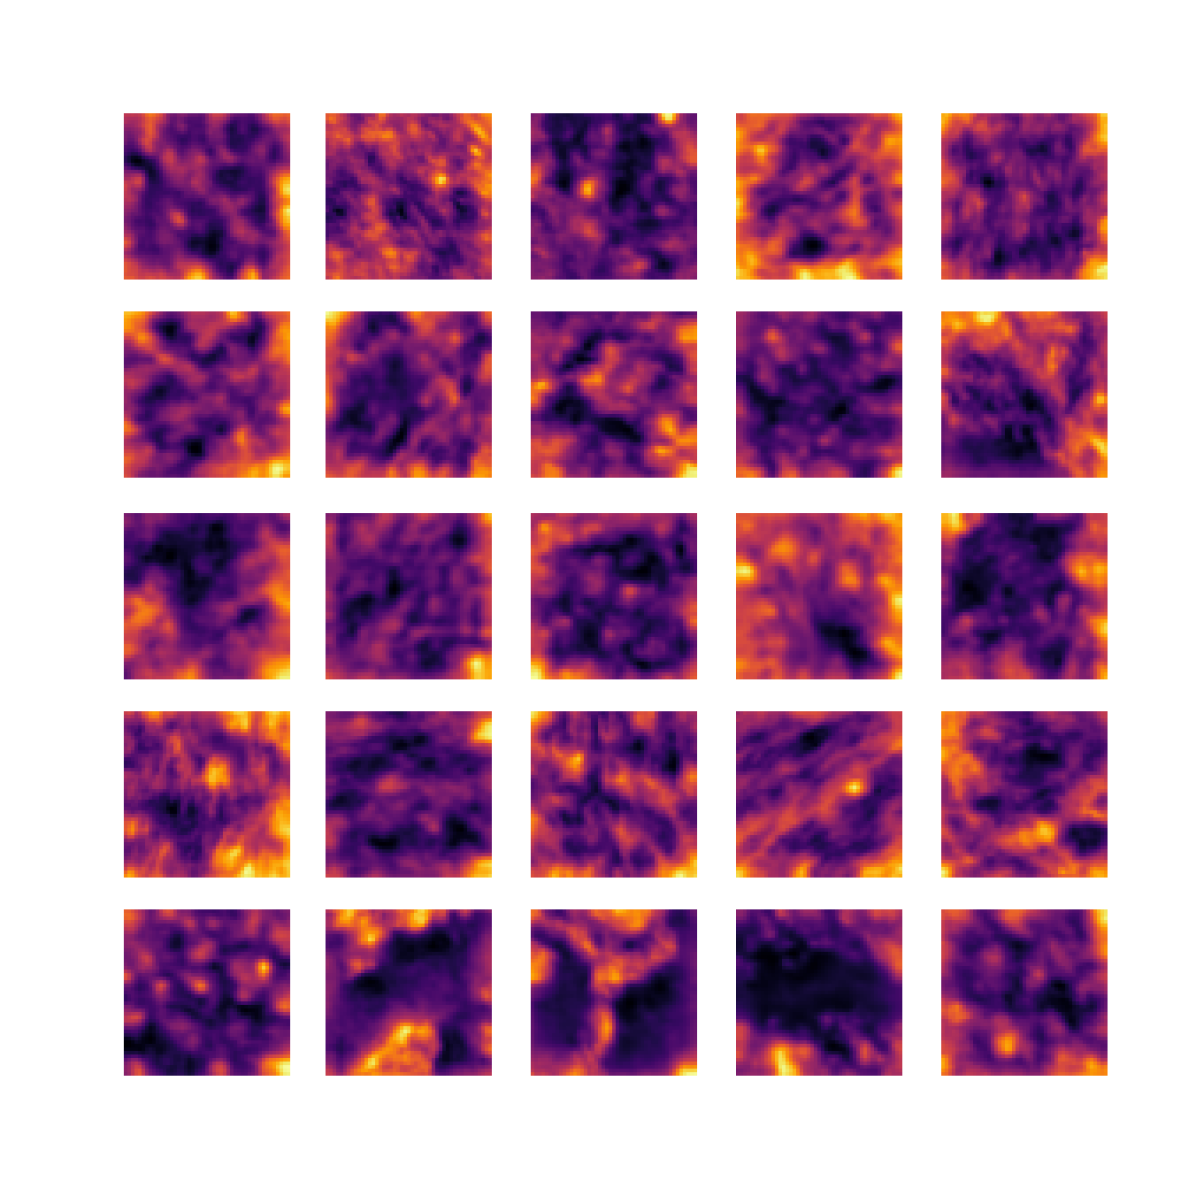

We also analyse the activation maps for each model using GradCAM as described in section S3. This offers more insight into the areas of the image which are contributing most heavily to the models’ representations. In Figure 4(b) we present some representative examples, however, a larger selection which was chosen at random is presented in Figures S10 to S25. The larger selection makes it easier to see the emergent patterns, including that privileged Siamese models tend to mainly identify features which are strongly present in both inputs, while unprivileged Siamese models tend to learn more diffuse features that are not specific to one cell phenotype or image region. TriDeNT ♆ incorporates both sets of features, learning both features specific to the privileged data and more the general features associated with unprivileged Siamese networks.

We can see in Figure 4(b) panel A that for ERG, the privileged Siamese model focuses almost exclusively on any nuclei which could be endothelial cells. As there are very few endothelial cells in the dataset, it could be an effective strategy to identify anything that could potentially be an endothelial cell to minimise the difference between the representations of the H&E model and the IF mask model. In the corresponding unprivileged Siamese image, we see that the model identifies some of these nuclei, albeit less strongly, but also focuses heavily on the other tissue and even the background, while strongly fixating on two spots of debris in the center of the image. This model has less ‘incentive’ to learn the weak features related to endothelial cells as these occur rarely and are not easy to detect, while more generic strong features such as the presence of connective tissue and the prevalence of background are more common and predictable from augmented images. We see that TriDeNT ♆ combines these two feature sets, strongly identifying nuclei while also identifying the connective tissue.

In panel C we see a similar pattern, with the privileged Siamese model fixating solely on the nuclei, while the TriDeNT ♆ model takes a more balanced approach. The unprivileged Siamese model appears to focus on a single cluster of nuclei while neglecting others, and similarly identifies an area of fibroblasts with its distinctive pattern but does not others.

In contrast to panels A and C which represent models with poor privileged Siamese results, panels B and D represent models whose privileged Siamese results were comparable to both TriDeNT ♆ and even the supervised baseline. It is therefore interesting to note that there are far more similarities between the privileged Siamese and TriDeNT ♆ models in both cases. Particularly in panel B, TriDeNT ♆ and the privileged Siamese model return virtually identical heatmaps, with both strongly identifying epithelial nuclei and neglecting the same areas of connective tissue. The unprivileged model in this case appears to focus solely on the centre of the image, giving a significantly different heatmap to the other panels.

Panel D again shows the previous pattern, with the privileged Siamese model identifying the features strongly present in the privileged data – fibroblasts – while neglecting the nuclei present. TriDeNT ♆ also strongly identifies the connective tissue, but, unlike the privileged Siamese model, does not completely neglect the nuclei. The unprivileged Siamese model primarily identifies background, and does not appear to identify the nuclei in this example.